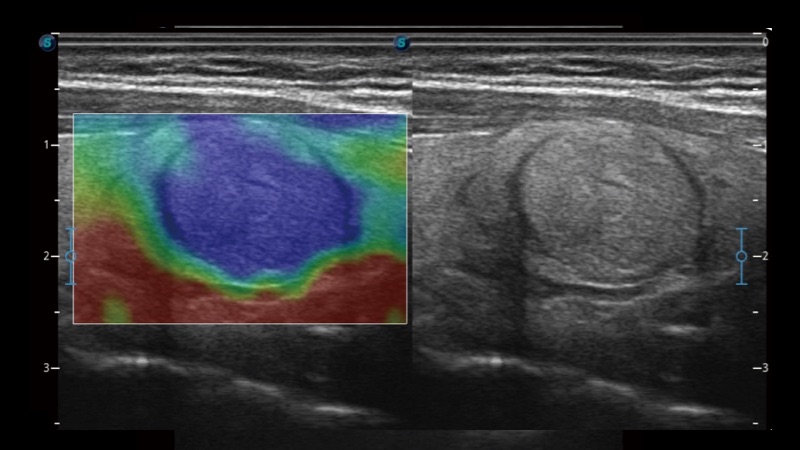

開立醫(yī)療通過不斷的技術(shù)創(chuàng)新,為大眾的生命健康提供持續(xù)關(guān)愛。P12 Plus采用全新一代超聲成像平臺,新平臺旨在將真實還原組織解剖結(jié)構(gòu)作為首要目標(biāo)。平臺采用全新集成化硬件模塊,搭載新一代芯片,系統(tǒng)性能得到大幅提升,為您的診斷提供了豐富的臨床信息。優(yōu)異的圖像表現(xiàn),豐富的探頭配置,全面的應(yīng)用功能,為您日常診斷提供了可靠的助手。

彩色多普勒超聲診斷系統(tǒng)